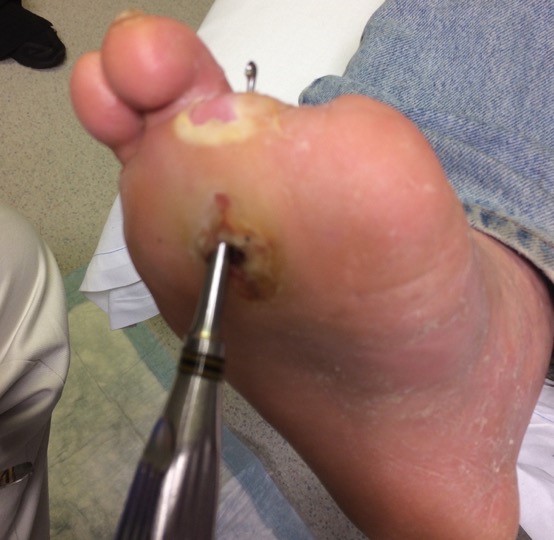

• Osteomyelitis: Wounds that are chronic, large, deep, or overlie a bony prominence are at high risk for underlying bone infection, the presence of a 'sausage toe' (Figure 11)  or visible bone is highly indicative of osteomyelitis.[8]

• International consensus [91] recommends performing a probe-to-bone test for infected wounds (Figure 12).[92]  In a patient at low risk for osteomyelitis (e.g., outpatient), a negative test largely rules out the diagnosis, while in a high-risk patient (i.e., inpatient), a positive test is largely diagnostic.[70][93]

Figure 12. Probe-to-bone in a DFU

• Probe-to-bone: all open infected DFU need to be inspected and gently probed with a sterile blunt metal probe (Figure 12). If the metal strikes bone (detected by its hard, gritty feel) in a patient at high risk for osteomyelitis, there is a high likelihood that the patient has osteomyelitis. Conversely, if no bone is detected (negative probe-to-bone test) in a patient at low risk, this essentially rules out osteomyelitis [70][72]. In practice, for all open infected DFU with positive probe-to-bone test, clinicians might opt for further imaging.